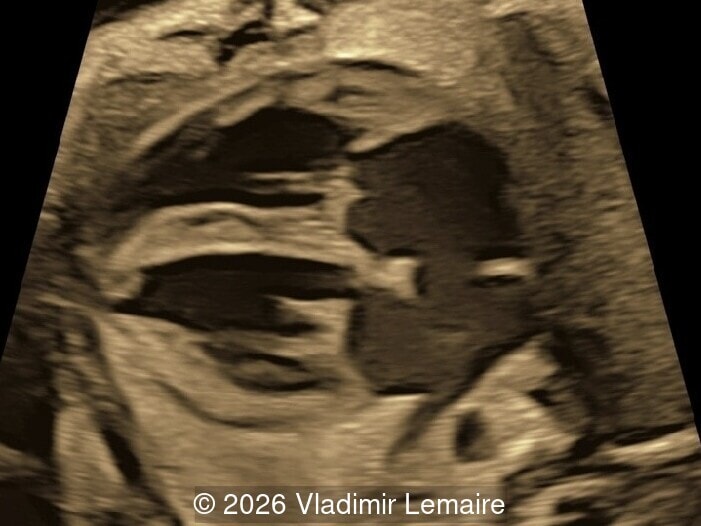

Surface mode rendering looking into the brain of the same fetus with the vein of Galen aneurysmal malformation.

Image 1 Surface mode rendering looking into the brain of the same fetus with the vein of Galen aneurysmal malformation.